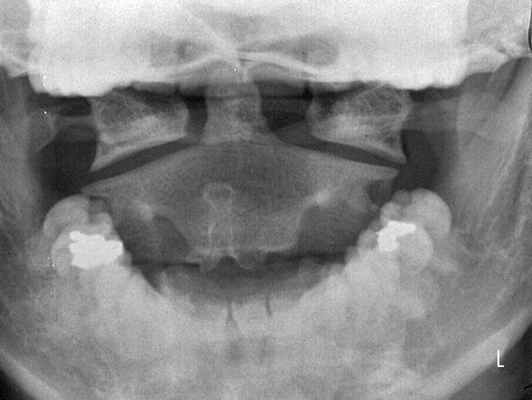

- ренгенографическое исследование шейного отдела ПС в боковой проекции

- Рентгеноконтрастное исследование (миелография). Для исключения других патологий — Компьютерная томография

Рентгеновский снимок позволяет достаточно четко визуализировать область АА сустава, преимущественно у карликовых пород собак, ввиду очень незначительной толщины позвонков (средняя толщина дорсальной дужки атланта в период с 1-3 месяцев составляет 1- 1.2 мм. (McCarthy R.J., Lewis D.D., 1995)). Также по ренгеновскому снимку можно оценить увеличение расстояния между позвонками С1 и С2.

Снимок, рекомендуется проводить без общей анестезии, так как расслабление и снятие болевого синдрома (если таковой имеется) усугубит повреждение спинного мозга, что может вследствие восходящего отека привести к параличу дыхательного центра и летальному исходу.

Рентгенологическое исследование является основным методом диагностики. Шейный отдел позвоночника исследуется в пяти проекциях:

- переднезадняя проекция;

- боковая;

- снимки в боковой проекции со сгибанием и разгибанием головы;

- прямой снимок через открытый рот. [3]

Этот стандарт исследования минимизирует возможность ошибок диагностики, так как подвывих иногда выявляется только на функциональных снимках. Исследование шейного отдела позвоночника в двух или трех стандартных проекциях не дает достаточной информации, чтобы диагностировать подвывих атланта, который часто остается нераспознанным. [4]